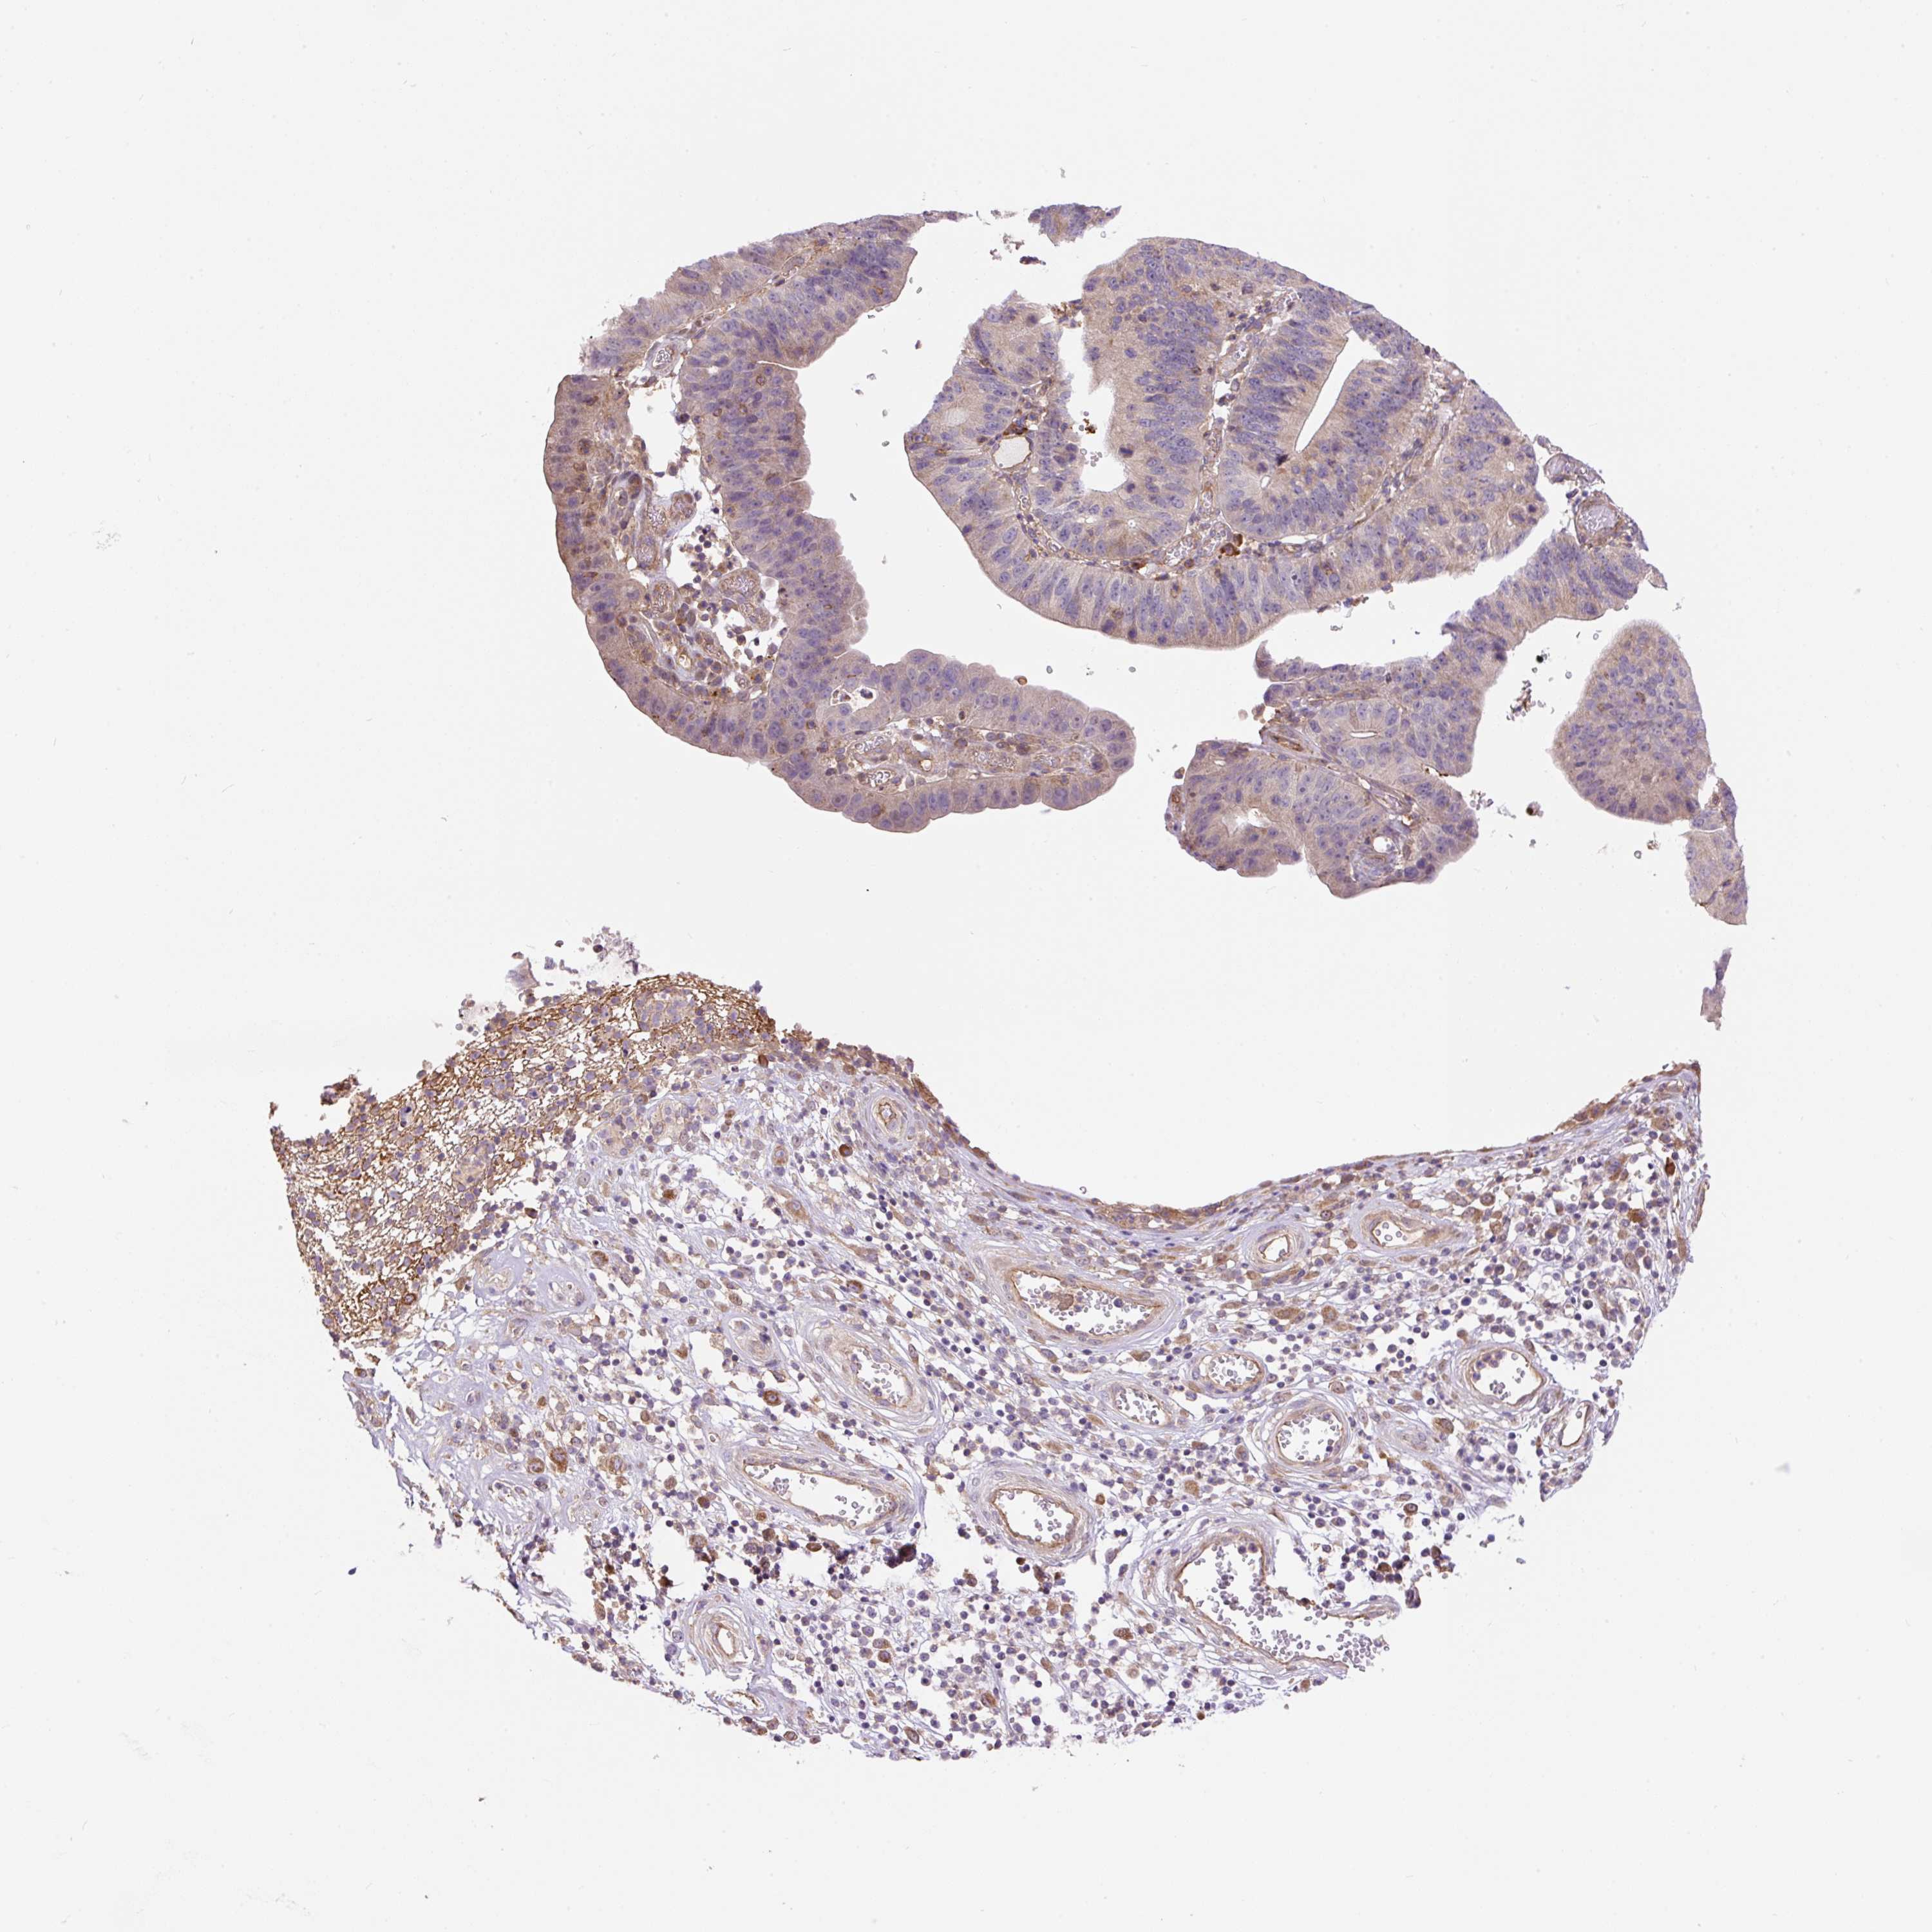

STOMACH CANCER - Protein expressioni

A mouse-over function shows sample information and annotation data. Click on an image to view it in a full screen mode. Samples can be filtered based on level of antibody staining by selecting one or several of the following categories: high, medium, low and not detected. The assay and annotation is described here.

Note that samples used for immunohistochemistry by the Human Protein Atlas do not correspond to samples in the TCGA dataset.

Antibody stainingi

Antibody staining in the annotated cell types in the current human tissue is reported as not detected, low, medium, or high, based on conventional immunohistochemistry profiling in selected tissues. This score is based on the combination of the staining intensity and fraction of stained cells.

Each image is clickable and will lead to virtual microscopy that enables deeper exploration of all samples and also displays staining intensity scores, fraction scores and subcellular localization as well as patient and tissue information for each sample.

Antibody HPA043900

Antibody CAB004541

Staining

High

Medium

Low

Not detected

Intensity

Strong

Moderate

Weak

Negative

Quantity

>75%

75%-25%

<25%

None

Location

Nuclear

Cytoplasmic/membranous

Cytoplasmic/membranous,nuclear

Adenocarcinoma, NOS

Adenocarcinoma, High grade